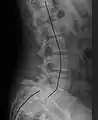

X-ray of the lateral lumbar spine with a grade III anterolisthesis at the L5-S1 level

• Grade III: 50–75%